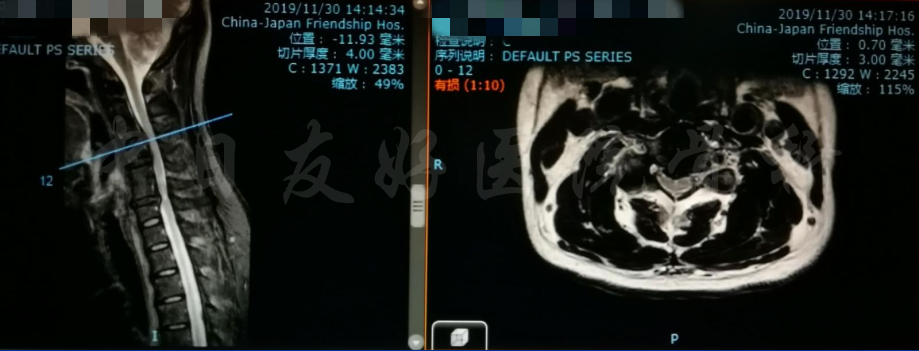

MRI

MRI颈4-5(左)、颈5-6(中)颈6-7(右)

矢状位MRI

轴位MRI:腰3-4(左)、腰4-5(中)、腰5骶1(右)

2019年11月30日 颈椎MRI提示:颈3/4颈4/5颈6/7椎间盘突出,椎管狭窄;颈5-6水平脊髓异常信号,变性可能。

颈椎MRI

颈椎MRI

颈椎各节段MRI(上下滑动)

腰椎MRI